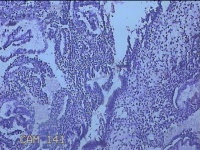

性别

女

年龄

41岁

临床诊断

异常子宫出血;取出子宫内节育器;子宫内膜炎

一般病史

阴道不规则流血2个月。

标本名称

宫腔内容物

大体所见

灰白暗红色不规则碎组织3.5x2.5x0.8cm一堆。